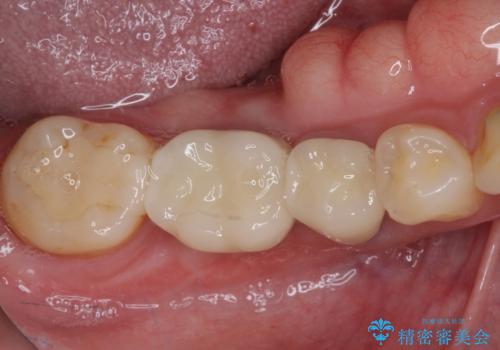

気になる部分を全て治療 総合歯科治療で口腔内環境改善

- 右下の欠損部の治療を希望して来院された患者様です。

部分矯正を行った後にインプラント埋入と手前の歯の根管治療を行い、その後補綴治療を行うこととしました。

治療途中より、上の歯や反対側の銀歯、上顎前歯の色合いや下顎前歯のデコボコが気になってきたため、全てを治療することとしました。